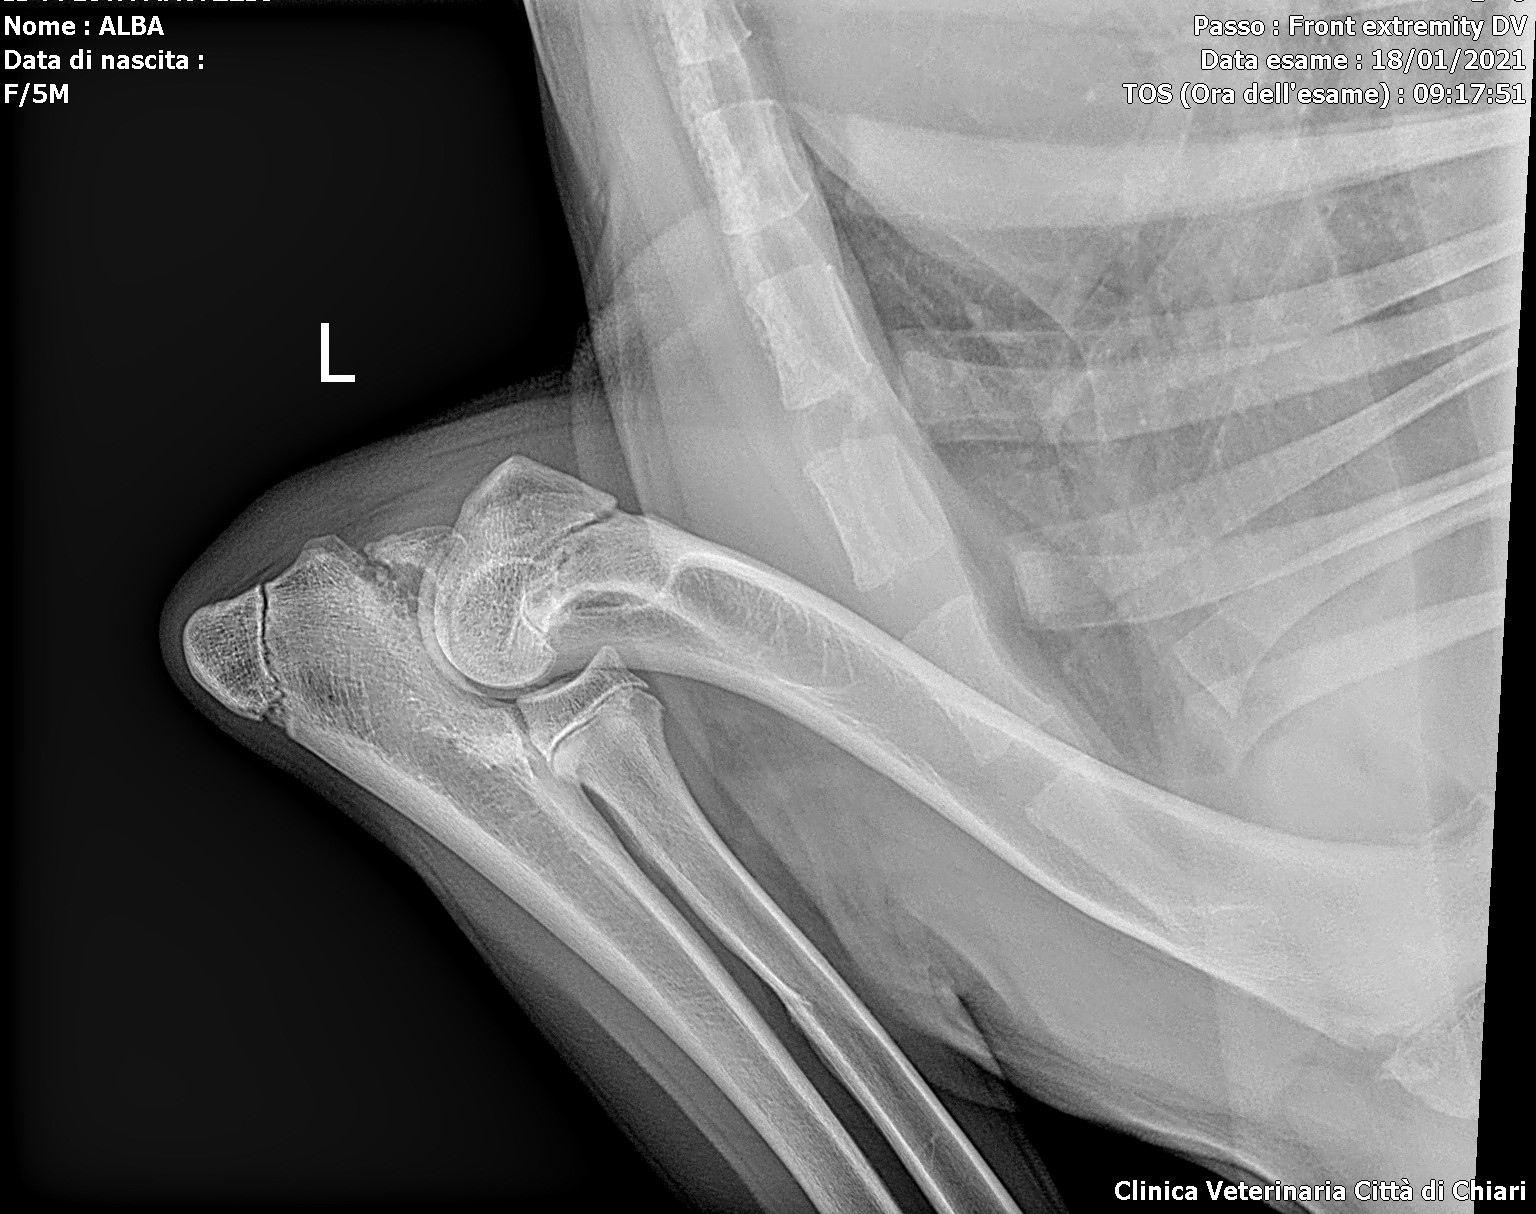

Processo Anconeo Unito (2)